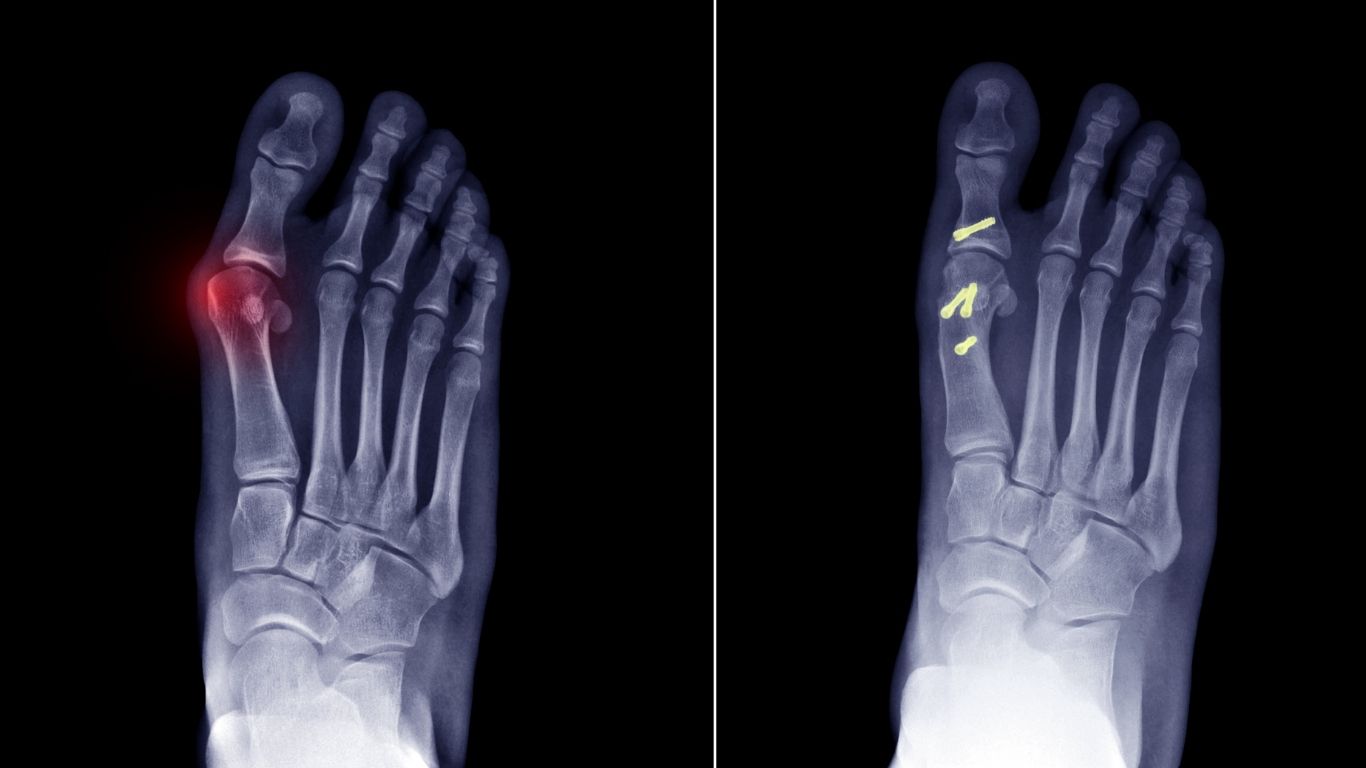

- Bone Fractures & Injuries: From simple to serious bone breaks, he provides the right treatment so you heal safely.

- Joint Pain & Arthritis: Pain in your knees, hips, or shoulders? He helps reduce pain and improve movement.

- Hip Replacement Surgery: For people who need a new hip joint to walk pain-free again.

- Fracture Treatment

- Arthritis and Joint Pain Treatment

- Hip Replacement Surgery

- Bone Scans (X-ray, MRI)